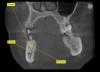

sergio Опубликовано 14 июня, 2013 Поделиться Опубликовано 14 июня, 2013 Артур, честные 35 Н/См там было.Сегодня бы сделала чуть по-другому - припаковала бы вестибулярно чуть ксено материала и сст с бугра плюс фдм.я вот до сих пор убежден, что немедленная импл. показана только вверху во фронте за счет наличия выраженной небной стенки. но вот пришла пациентка, ей в нескольких местах сказали, что можно одномоментно в области зуба 4.5. что-то я сомневаюсь, помогите с выбором, она настроена на такой протокол. Но там нет 5 мм апикальнее дна лунки для хорошей стабилизации. Стася, хотелось бы увидеть ваши снимки Ссылка на комментарий